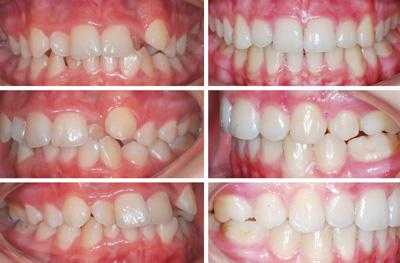

В полости рта дистальный прикус определяется по выступающим вперед верхним фронтальным зубам. В норме, при ортогнатическом прикусе, верхние резцы перекрывают нижние примерно на 1/3. При дистальной патологии между верхними и нижними резцами образуется расстояние — «саггитальная щель».

Саггитальная щель и прикус в норме

- Фотопротокол. Для оценки состояния прикуса и полости рта на диагностике фиксируются на фото зубы с разных ракурсов, в сомкнутом, несомкнутом состоянии, а, также, лицо в профиль, анфас, с улыбкой, с открытым и закрытым ртом. Снимки помогают отслеживать динамику лечения, корректировать и оценить финальный результат лечения.